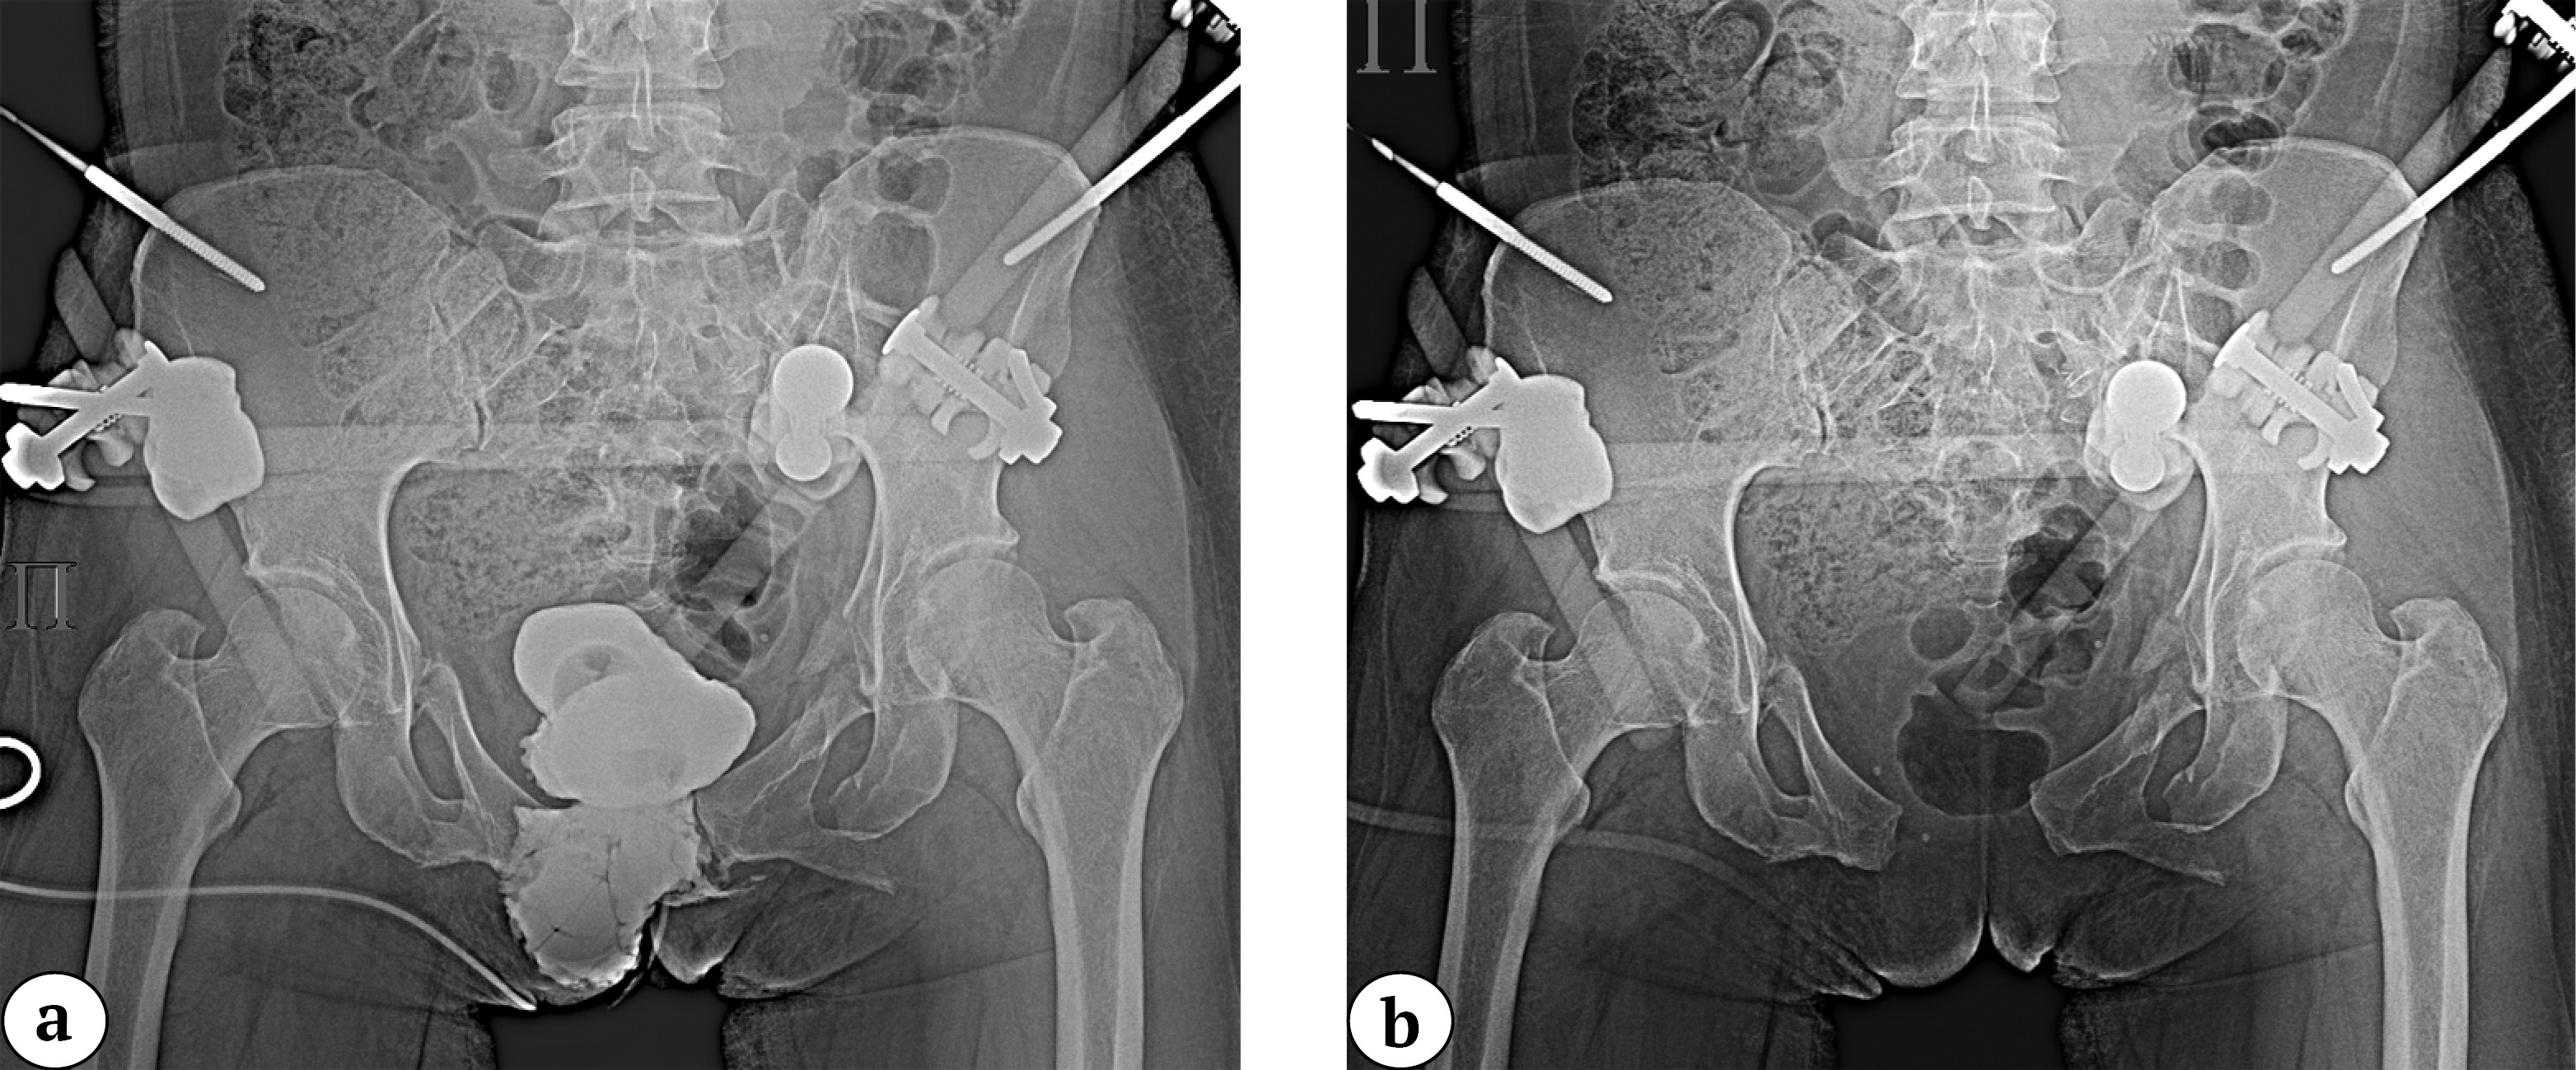

Standard positioning of the plate after osteosynthesis and the view of the surgical field prior to closure are shown below (Figure 6).

Figure 6. Intraoperative anteroposterior view of the pelvis after combined fixation with the nail-plate system (a); intraoperative photograph of the surgical site prior to wound closure (b)

During the clinical phase, when performing this surgical technique, patients underwent drainage of the Retzius space using a Redon drain through a contralateral incision in the area of the Hesselbach triangle. The surgical field was irrigated with saline and closed in layers. Postoperative sutures were covered with a sterile dressing. Before wound closure, the absence of blood in the urinary catheter was verified.